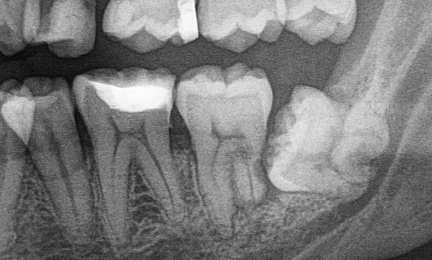

Za pojmom OPG sa skrýva panoramatická snímka hornej aj dolnej čeľusti s kĺbom a prínosovými dutinami. Na ňom môže zubár spozorovať napríklad kazy pod plombami, zápaly a zistí, kde sa nachádzajú neprerezané zuby. Okrem toho možno odhaliť možné príčiny paradontózy ako aj krvácania z ďasien.

Bite-wing, alebo po slovensky aj záhryzová snímka, vie skvele odhaliť kazy medzi zubami alebo pod plombami, ktoré inak sa nedajú v ústach vidieť.